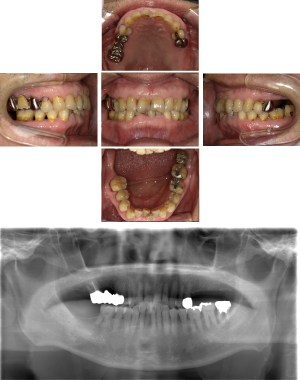

50代 インプラント治療(右上3左上3のみGBR)

| 年代・性別 | 50代・男性 |

| 主訴 | 入れ歯が合わず毎日ヨーグルトしか食べることができないので、しっかり咬めるインプラントにしたい。 |

| 部位 | 右下⑦⑥5④ 上顎③2①①2③ 左下67 |

| 治療期間 | 約9ヶ月 |

| 費用 | ¥4,273,500(税込) |

| 副作用・リスク |

|